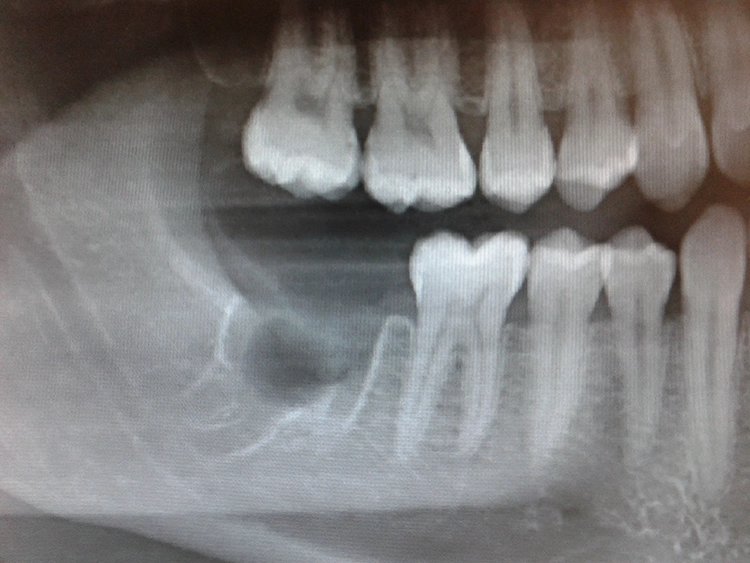

Zahnresorptionen an der distalen Radix der 2. Molaren stellen einen äußerst schwierigen Befund dar. Zum einen wird versucht, jeden Zahn zu erhalten, jedoch kann es selbst mit den neuesten endodontischen Mitteln manchmal nicht möglich sein. In der konventionellen Panoramaschichtaufnahme ist die Bewertung einer Resorption an den Nachbarzähnen ausgesprochen unsicher (Abb. 1 bis 4).

„Mit der Ausweitung der DVT-Bildgebung ist zu erwarten, dass Resorptionen an 12-Jahr-Molaren zukünftig häufiger erkannt und in die Entscheidung über eine Weisheitszahnentfernung einbezogen werden müssen. Epidemiologische Daten zur Häufigkeit stehen zwar noch aus, Patientenserien mit einer Prävalenz um 20% bei horizontal und mesioangulär inklinierten 3. Molaren lassen aber erwarten, dass der Problematik externer Resorptionen zukünftig ein relevanter Stellenwert in der Therapie entscheidung zukommen wird.“ [2] Falls möglich und der Patient sich in kieferorthopädischer Therapie befindet, stellt die kieferorthopädische Einstellung des Weisheitszahnes nach Entfernung des zerstörten bzw. anresorbierten 2. Molaren eine gut prognostizierbare und zufriedenstellende Therapielösung dar.